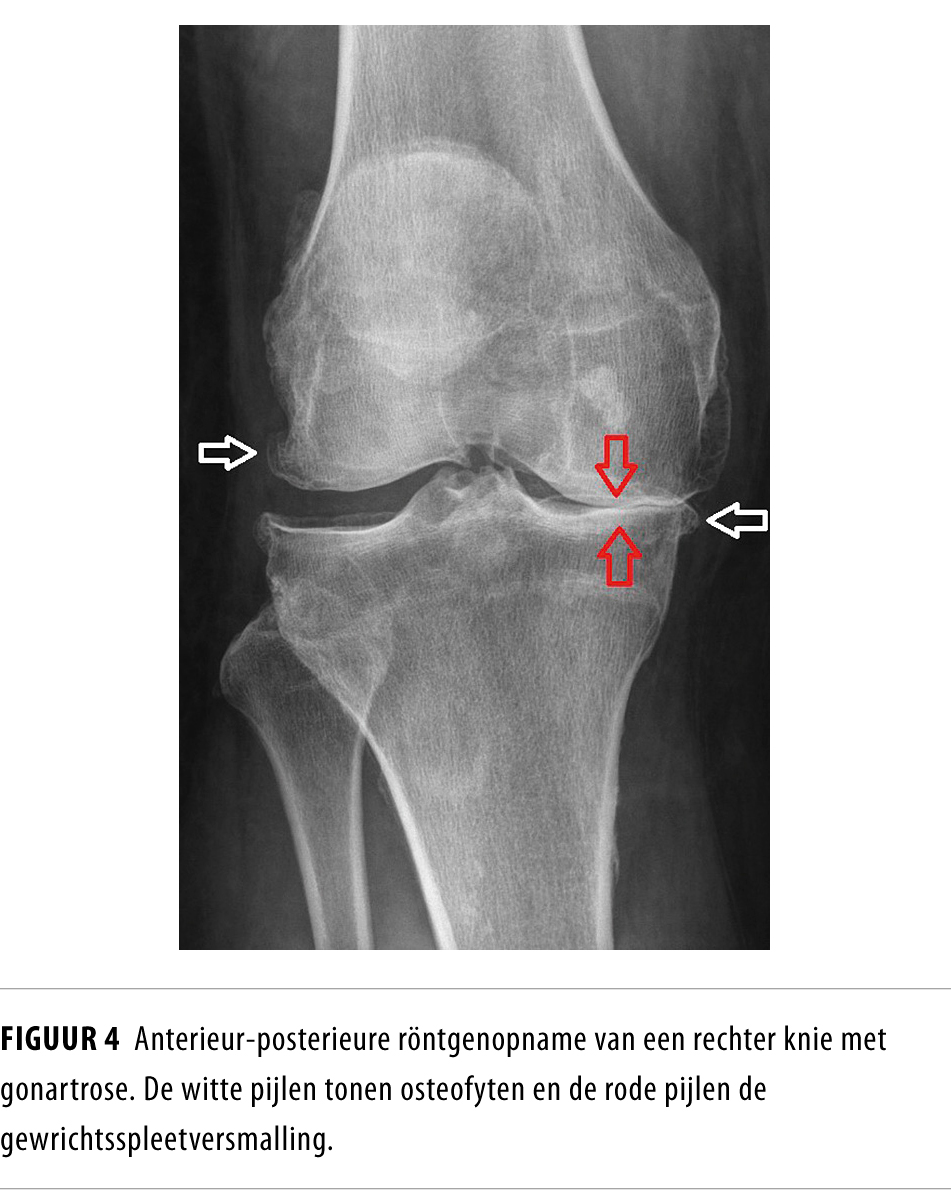

Vroeger werd artrose gezien als slijtage die leidt tot gewrichtsweefselschade en uiteindelijk tot een functiebeperking. Maar tegenwoordig wordt ze beschouwd als een uiterst complexe, multifactoriële, degeneratieve ziekte. Deze invaliderende aandoening begint op latere leeftijd en wordt gekenmerkt door verlies van articulair kraakbeen en ontsteking van het synoviale weefsel.

Waar artrose voorheen werd gezien als alleen gewrichtsslijtage, beschouwt men haar nu als een uiterst complexe, multifactoriële, degeneratieve ziekte. Door de vergrijzing en de toenemende BMI van de gemiddelde Nederlander zullen de prevalentie van artrose en de daaraan gerelateerde zorgkosten stijgen. In dit leerartikel geven wij praktische informatie over het ziektebeeld, de diagnostiek en de behandeling. Dit doen wij aan de hand van 10 vragen die leven bij onder anderen huisartsen, internisten en chirurgen.